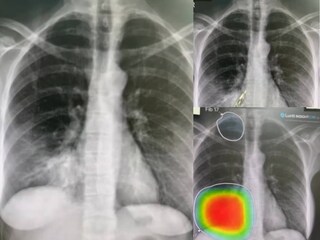

രോഗിയുടെ എക്സ്-റേ വിശകലനം ചെയ്യാന് ഒരു എഐ സാങ്കേതികവിദ്യ ഉപയോഗപ്പെടുത്തികൊണ്ടായിരുന്നു അദ്ദേഹത്തിന്റെ പരീക്ഷണം. അദ്ദേഹത്തിന്റെ നിരീക്ഷണവും എഐയുടെ കണ്ടെത്തലും സമാനമാണ് ഈ പരീക്ഷണത്തിൽ നിന്നും മനസ്സിലാക്കി. ഇതാണ് തന്റെ ജോലിയുടെ ഭാവി സംബന്ധിച്ച ആശങ്കകളിലേക്ക് അദ്ദേഹത്തെ നയിച്ചത്.

"അപ്പോള് എനിക്ക് എന്റെ ജോലി നഷ്ടപ്പെടാന് പോകുന്നു. ഇത് ഭായനകമാണ്", അദ്ദേഹം ഇന്സ്റ്റഗ്രാമില് പങ്കുവെച്ച വീഡിയോ പോസ്റ്റില് പറഞ്ഞു. ഒരു രോഗിയുടെ എക്സ് -റേ നോക്കി ന്യൂമോണിയ ഉണ്ടെന്നറിയാന് തനിക്ക് കഴിയുമെന്നും 20 വര്ഷത്തിലധികം എടുത്താണ് ഈ കഴിവ് താന് ആര്ജിച്ചതെന്നും ഒരാളുടെ ശ്വാസകോശത്തിന്റെ എക്സ്-റേയിലേക്ക് വിരല് ചൂണ്ടി അദ്ദേഹം പറഞ്ഞു.

പിന്നീട് അദ്ദേഹം എഐ ടൂള് ഉപയോഗിച്ച് ചെയ്ത രണ്ട് വ്യത്യസ്ത സ്കാന് കാണിച്ചു. അതിലും അദ്ദേഹം രോഗിക്ക് ന്യുമോണിയ നിര്ണയിക്കാന് ചൂണ്ടിക്കാണിച്ച ഭാഗങ്ങള് സമാനവും കൃത്യവുമായിരുന്നു. എക്സ്- റേ അടക്കമുള്ളവ നോക്കി രോഗ നിര്ണയം നടത്താന് ഇനി പ്രൊഫഷണല് ഡോക്ടര്മാരുടെ ആവശ്യമില്ലെന്നും എഐ സെക്കന്ഡിനുള്ളില് ഈ ജോലി ചെയ്യുമെന്നും അദ്ദേഹം പോസ്റ്റില് വിശദീകരിക്കുന്നുണ്ട്.

അതുകൊണ്ട്, താന് മക്ഡൊണാള്ഡിൽ അപേക്ഷിക്കാന് പോകുകയാണെന്നും അവിടെ ഒഴിവുകള് ഉണ്ടാകുമെന്നാണ് പ്രതീക്ഷിക്കുന്നതെന്നും അദ്ദേഹം അഭപ്രായപ്പെട്ടു. അതേസമയം, സ്കാനിങ്ങില് താന് ശ്രദ്ധിക്കാതിരുന്ന ഒരു അസാധാരണത്വം എഐ കണ്ടെത്തിയതായി അദ്ദേഹം പറയുന്നുണ്ട്. ഇതിന് ഡോക്ടര് സാങ്കേതികവിദ്യയെ പ്രശംസിച്ചു. അവസ്ഥയ്ക്ക് മരുന്ന് നിര്ദ്ദേശിച്ചതിനുശേഷം രോഗി സുഖം പ്രാപിക്കാന് തുടങ്ങിയെന്നും ഡോക്ടര് വ്യക്തമാക്കി.